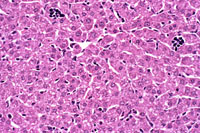

Extramedullary hematopoiesis (EMH) can occur in the liver, especially when there is long-standing anemia. Typical morphological features consist of small aggregates of cells with intensely basophilic nuclei (erythroid) or small collections of immature and mature myelocytic cells (myelopoiesis) located in the sinusoids and, in severe cases, in portal areas.

Multiple aggregates of neutrophilic band cells and erythroid precursor cells are present in the sinusoids with a large aggregate in a portal area.